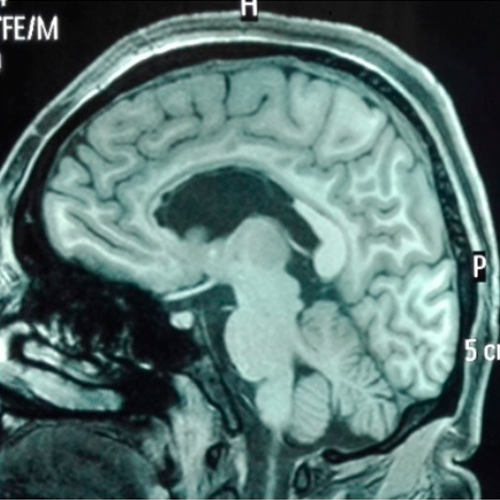

• Lobectomía temporal anterior estándar:

• Es el procedimiento quirúrgico realizado con más frecuencia en el mundo. Está indicado en pacientes con epilepsia refractaria del lóbulo temporal, en donde se ha determinado una adecuada correlación clínica, eléctrica e imagenológica. En algunos casos se plantea una cirugía de menor extensión como la llamada amigdalohipocampectomía selectiva, este procedimiento se realiza generalmente cuando el paciente tiene una epilepsia localizado en el lado dominante del paciente es decir en lado donde está localizado el lenguaje.